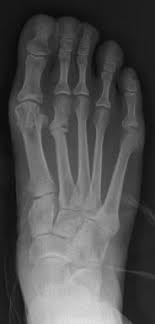

A stress fracture is a fatigue-induced bone fracture caused by repeated stress over time. Instead of resulting from a single severe impact, stress fractures are the result of accumulated injury from repeated submaximal loading, such as running or jumping. Because of this mechanism, stress fractures are common overuse injuries in athletes. Stress fractures can be described as small cracks in the bone, or hairline fractures. Stress fractures of the foot are sometimes called "march fractures" because of the injury's prevalence among heavily marching soldiers. Stress fractures most frequently occur in weight-bearing bones of the lower extremities, such as the tibia and fibula (bones of the lower leg), metatarsal and navicular bones (bones of the foot). Less common are stress fractures to the femur, pelvis, and sacrum. Treatment usually consists of rest followed by a gradual return to exercise over a period of months. From Wikipedia